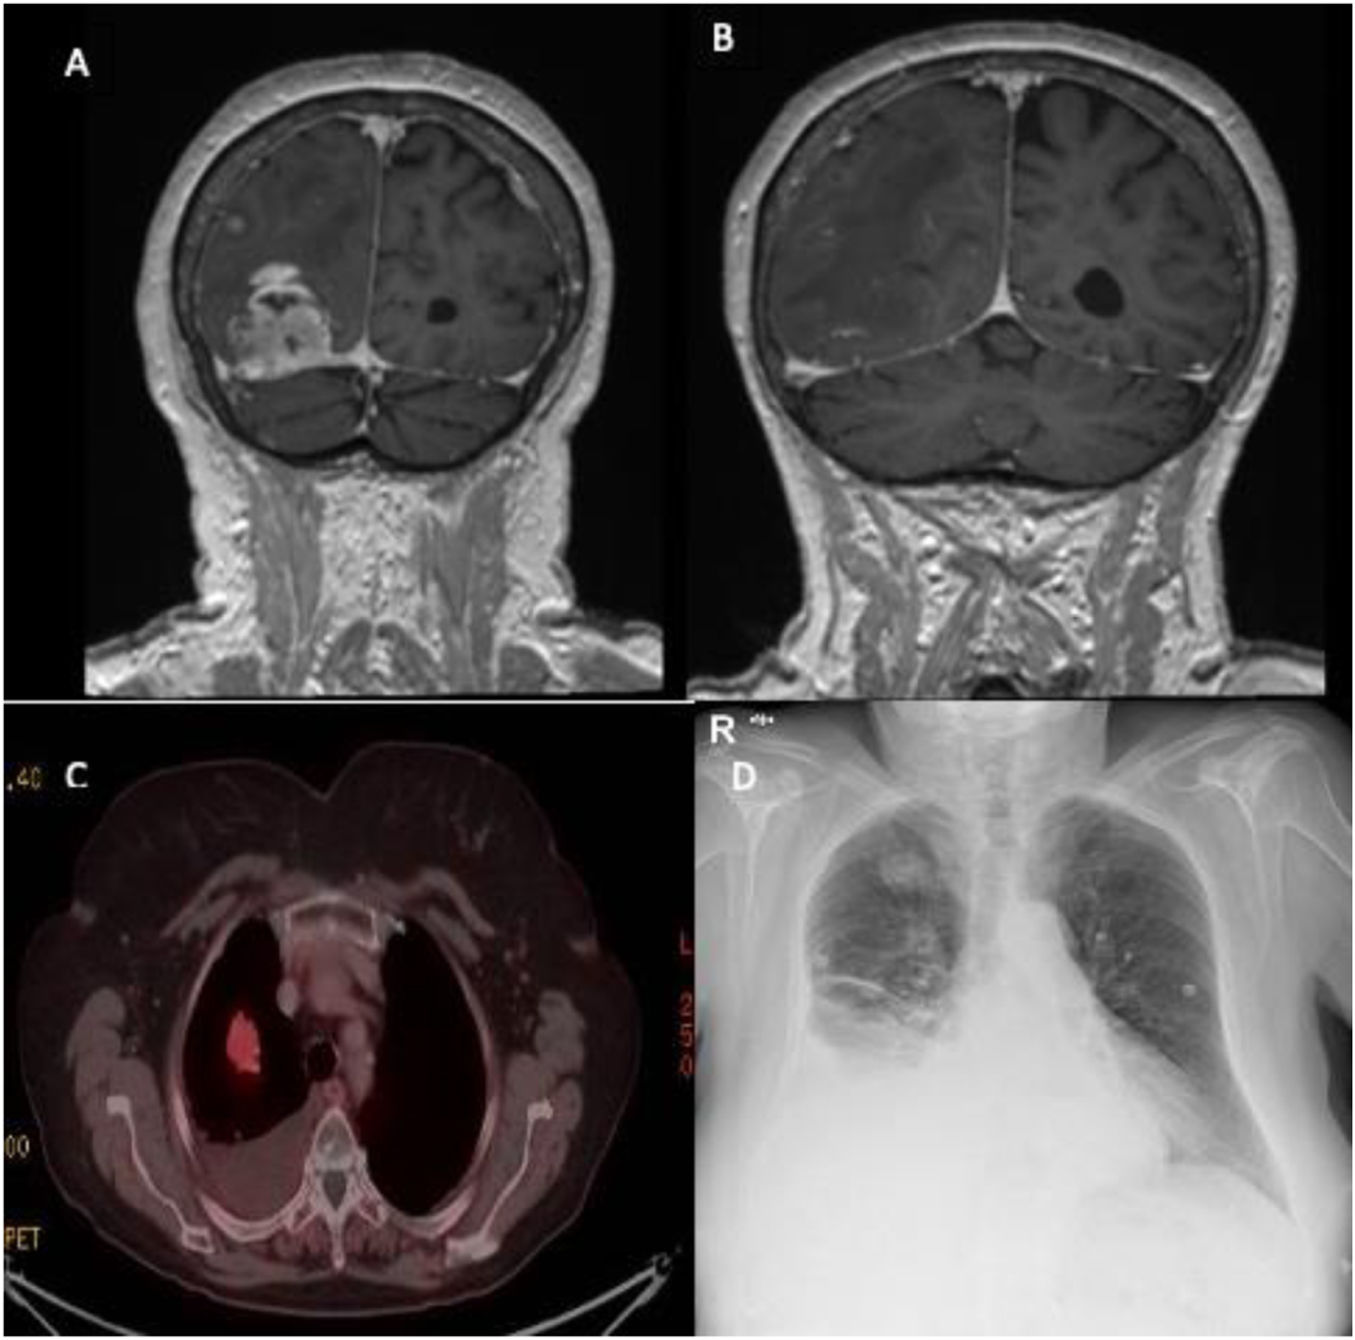

Tacrolimus is an essential immunosuppressive drug in lung transplantation. It is metabolized by cytochrome P450, which can cause interactions with many drugs. We present a case of acute tacrolimus poisoning in a lung transplant patient […]